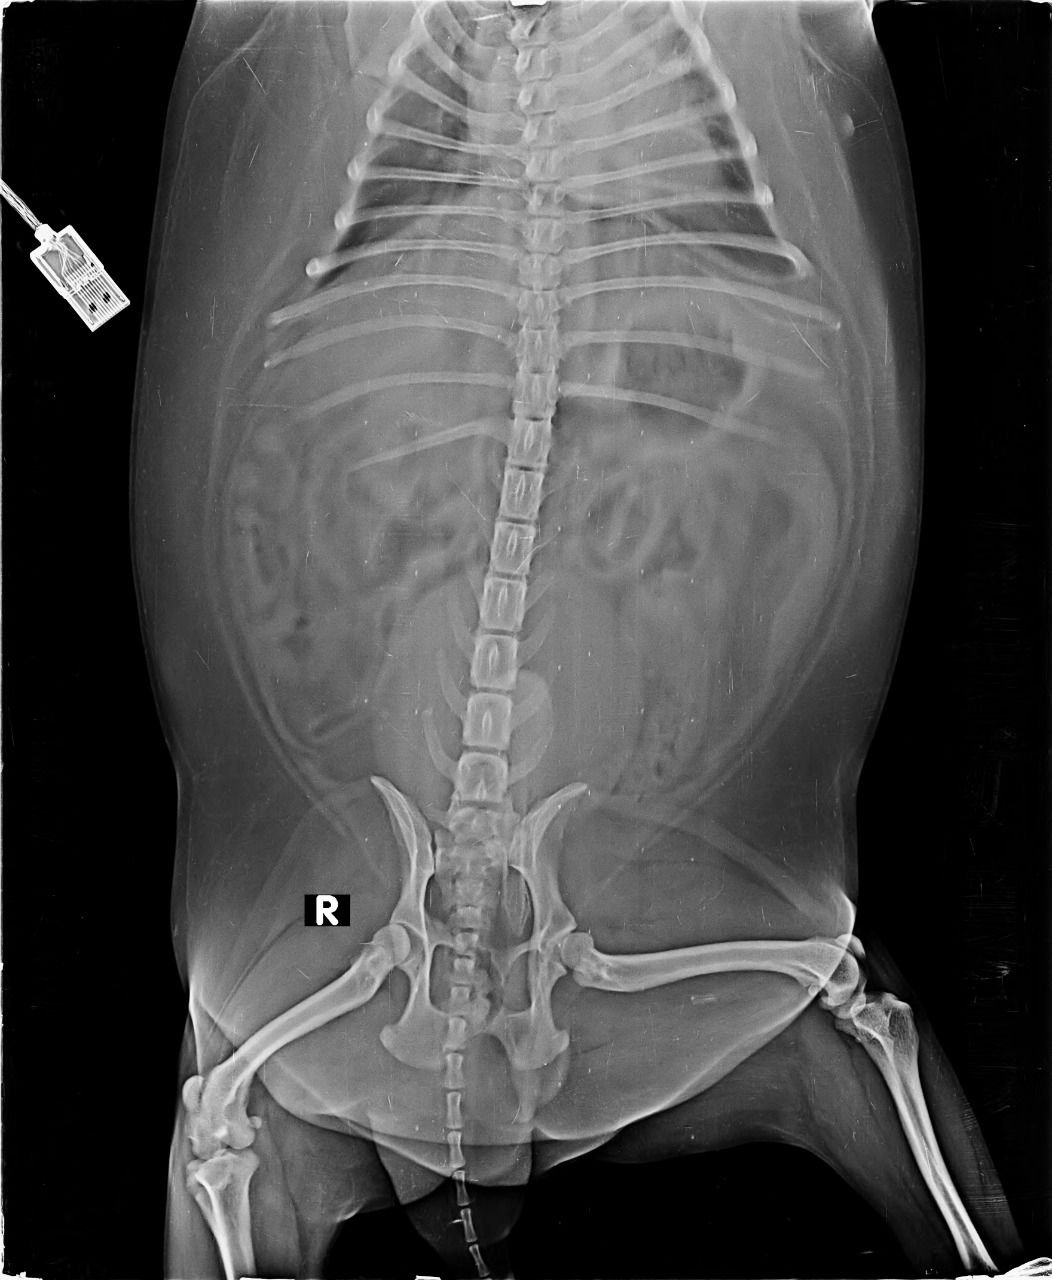

With a aim of “सर्वे भवन्तु सुखिनःI सर्वे सन्तु निरामया:I”, X RAY HOUSE, ANAND started Animal Imaging department for small animals.

We are pioneer of radio-diagnosis in small animals like dog, cat, rabbit, turtle etc. in Gujarat.